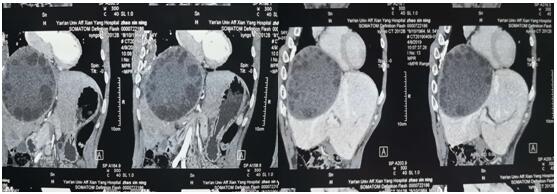

术前CT和三维重建

患者入科,姚春和主任与科室医师通过细致的诊查,即确诊该患者系“肝脏巨大肝包虫”。此病例较为罕见,手术难度大。经严密术前讨论,姚主任操刀,于4月16日在全麻下行巨大肝包虫外囊摘除术。术中严格无菌保护周围组织,细致剥离血管,手术历经4小时,成功摘除大小约20*30cm包虫外囊。此例手术的完成标志着我院肝胆外科在肝脏手术的又一巨大突破。